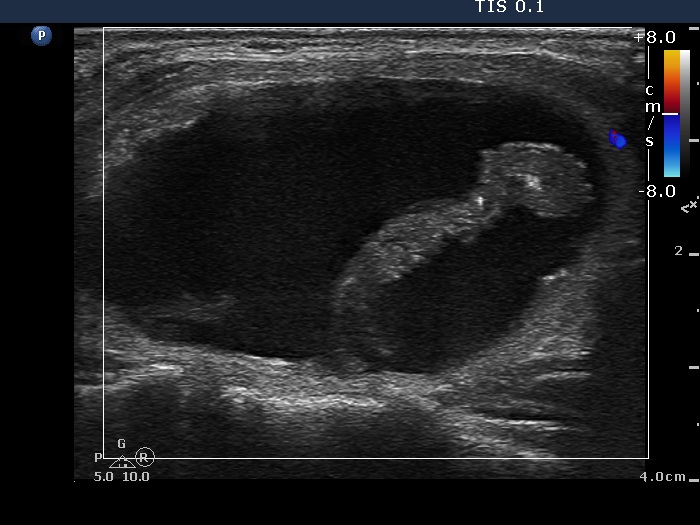

Ethanol sclerotherapy: other examples - Case 3: treatment of a gelatinous thyroid cyst

Second session of therapy (ultrasonographic picture 3)

Right lobe, longitudinal scan, color Doppler mode. The lesions does not present signs of blood flow.